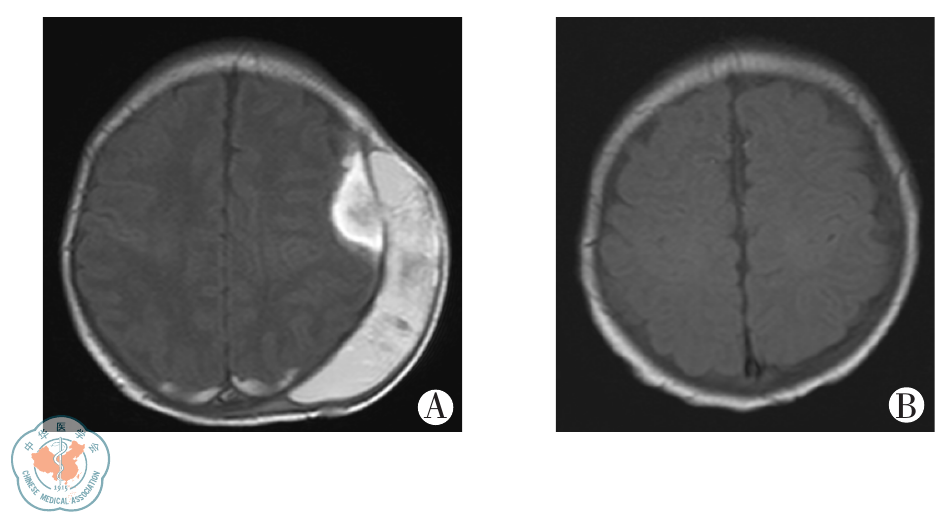

图1 颅内出血患儿头颅MRI图像 A为ECMO后4 d脑MRI示双侧顶枕部硬膜下、小脑幕下少许出血、左侧额颞部明显硬膜下血肿和头皮下巨大血肿;B为1个月后复查MRI示血肿基本吸收